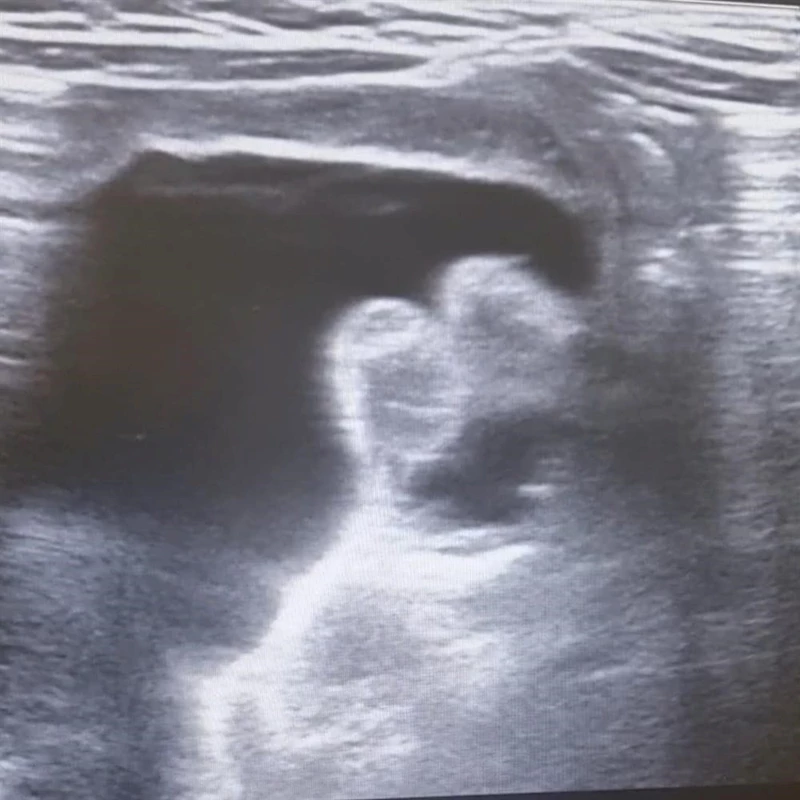

Edinilen bilgilere göre, kanlı ishal ve genel durum bozukluğu nedeniyle Hitit Üniversitesi Erol Olçok Eğitim ve Araştırma Hastanesi'ne kaldırılan 9 aylık bebeğe halk arasında "bağırsak düğümlenmesi'' olarak bilinen invajinasyon tanısı konuldu. Yapılan değerlendirmeler neticesinde invajinasyonun düzeltilmesi için transrektal yoldan işlem yapılması kararı alındı. Radyoloji Kliniği Eğitim Görevlisi ve Çocuk Radyolojisi Uzmanı Doç. Dr. Altan Güneş ve Çocuk Cerrahisi Kliniği Eğitim Görevlisi Prof. Dr. Çağatay Evrim Afşarlar tarafından acil serviste bebeğin düğümlenen bağırsağı ameliyata ihtiyaç kalmadan tedavi edildi.

Konu hakkında bilgi veren Çocuk Radyolojisi Uzmanı Doç. Dr. Altan Güneş, "İnvajinasyon veya halk arasındaki adıyla barsak düğümlenmesi, çocuk hastalarda sık görülen, erken tanı ve tedavi gerektiren, genellikle kanlı ishal, karın ağrısı ve genel durum bozukluğu gibi şikayetlerle hastaneye başvuru sebebi olan, tedavi edilmediği takdirde barsak delinmesi, barsak kaybı ve ağır vakalarda ölüme kadar gidebilecek ciddi bir acil durumdur. Tedavisinde ameliyata alternatif seçeneklerden birisi olarak ultrasonografi eşliğinde redüksiyon seçkin merkezlerde uygulanan bir tedavi yöntemidir. Bu sayede hastaların hastanede kalış süresi azalmakta, hastalar cerrahi yöntemlerin olumsuz yan etkilerinden korunmakta ve hızla, bazen aynı gün iyileşebilmektedirler'' dedi.